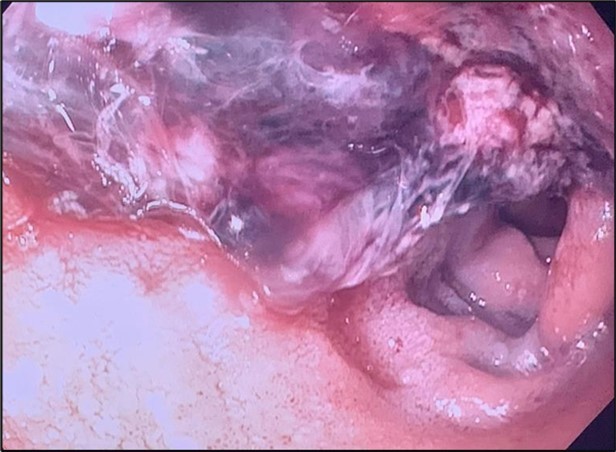

Image 1.Duodenal ulcer with large adherent clot.

A proton pump inhibitor infusion was started, and urgent upper endoscopy showed a 4 cm non-obstructing, deeply cratered duodenal ulcer with a large clot and diffuse oozing (Image 1). Hemostasis was achieved with the use of mineral powder that provides physical compression and promotes clotting. The lesion was not amenable to other forms of treatment given its size. She was subsequently extubated and transferred to the medical floor, where she had recurrence of melena. The patient’s melanotic stools self-resolved, but a continuously increasing alkaline phosphatase was noted, which prompted further workup (Figure 1).